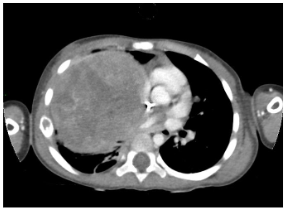

In the postnatal period, the gold standard remains contrast-enhanced computed tomography (CT angiography), which enables high-resolution evaluation of the bronchial tree integrity, characterization of parenchymal architecture (Figure 4), and assessment of the number and size of cysts (Figure 2). It also allows for precise visualization of aberrant systemic vessels (Figure 5), as well as evaluating compressive effects on mediastinal structures.

Postnatal magnetic resonance imaging (MRI) has gained ground as a radiation-free alternative, particularly relevant in infants and for long-term follow-up. High-resolution MRI can allow postponement of CT angiography in asymptomatic neonates until surgery, thereby avoiding early exposure to ionizing radiation. The introduction of ultrashort echo time (UTE) and zero echo time (ZTE) sequences has overcome traditional limitations of thoracic MRI by allowing visualization of aerated lung parenchyma. Furthermore, dynamic MRI sequences have opened a new dimension in functional assessment by enabling ventilation and perfusion studies, which are particularly useful when functional impairment exceeds what is suggested by structural findings.